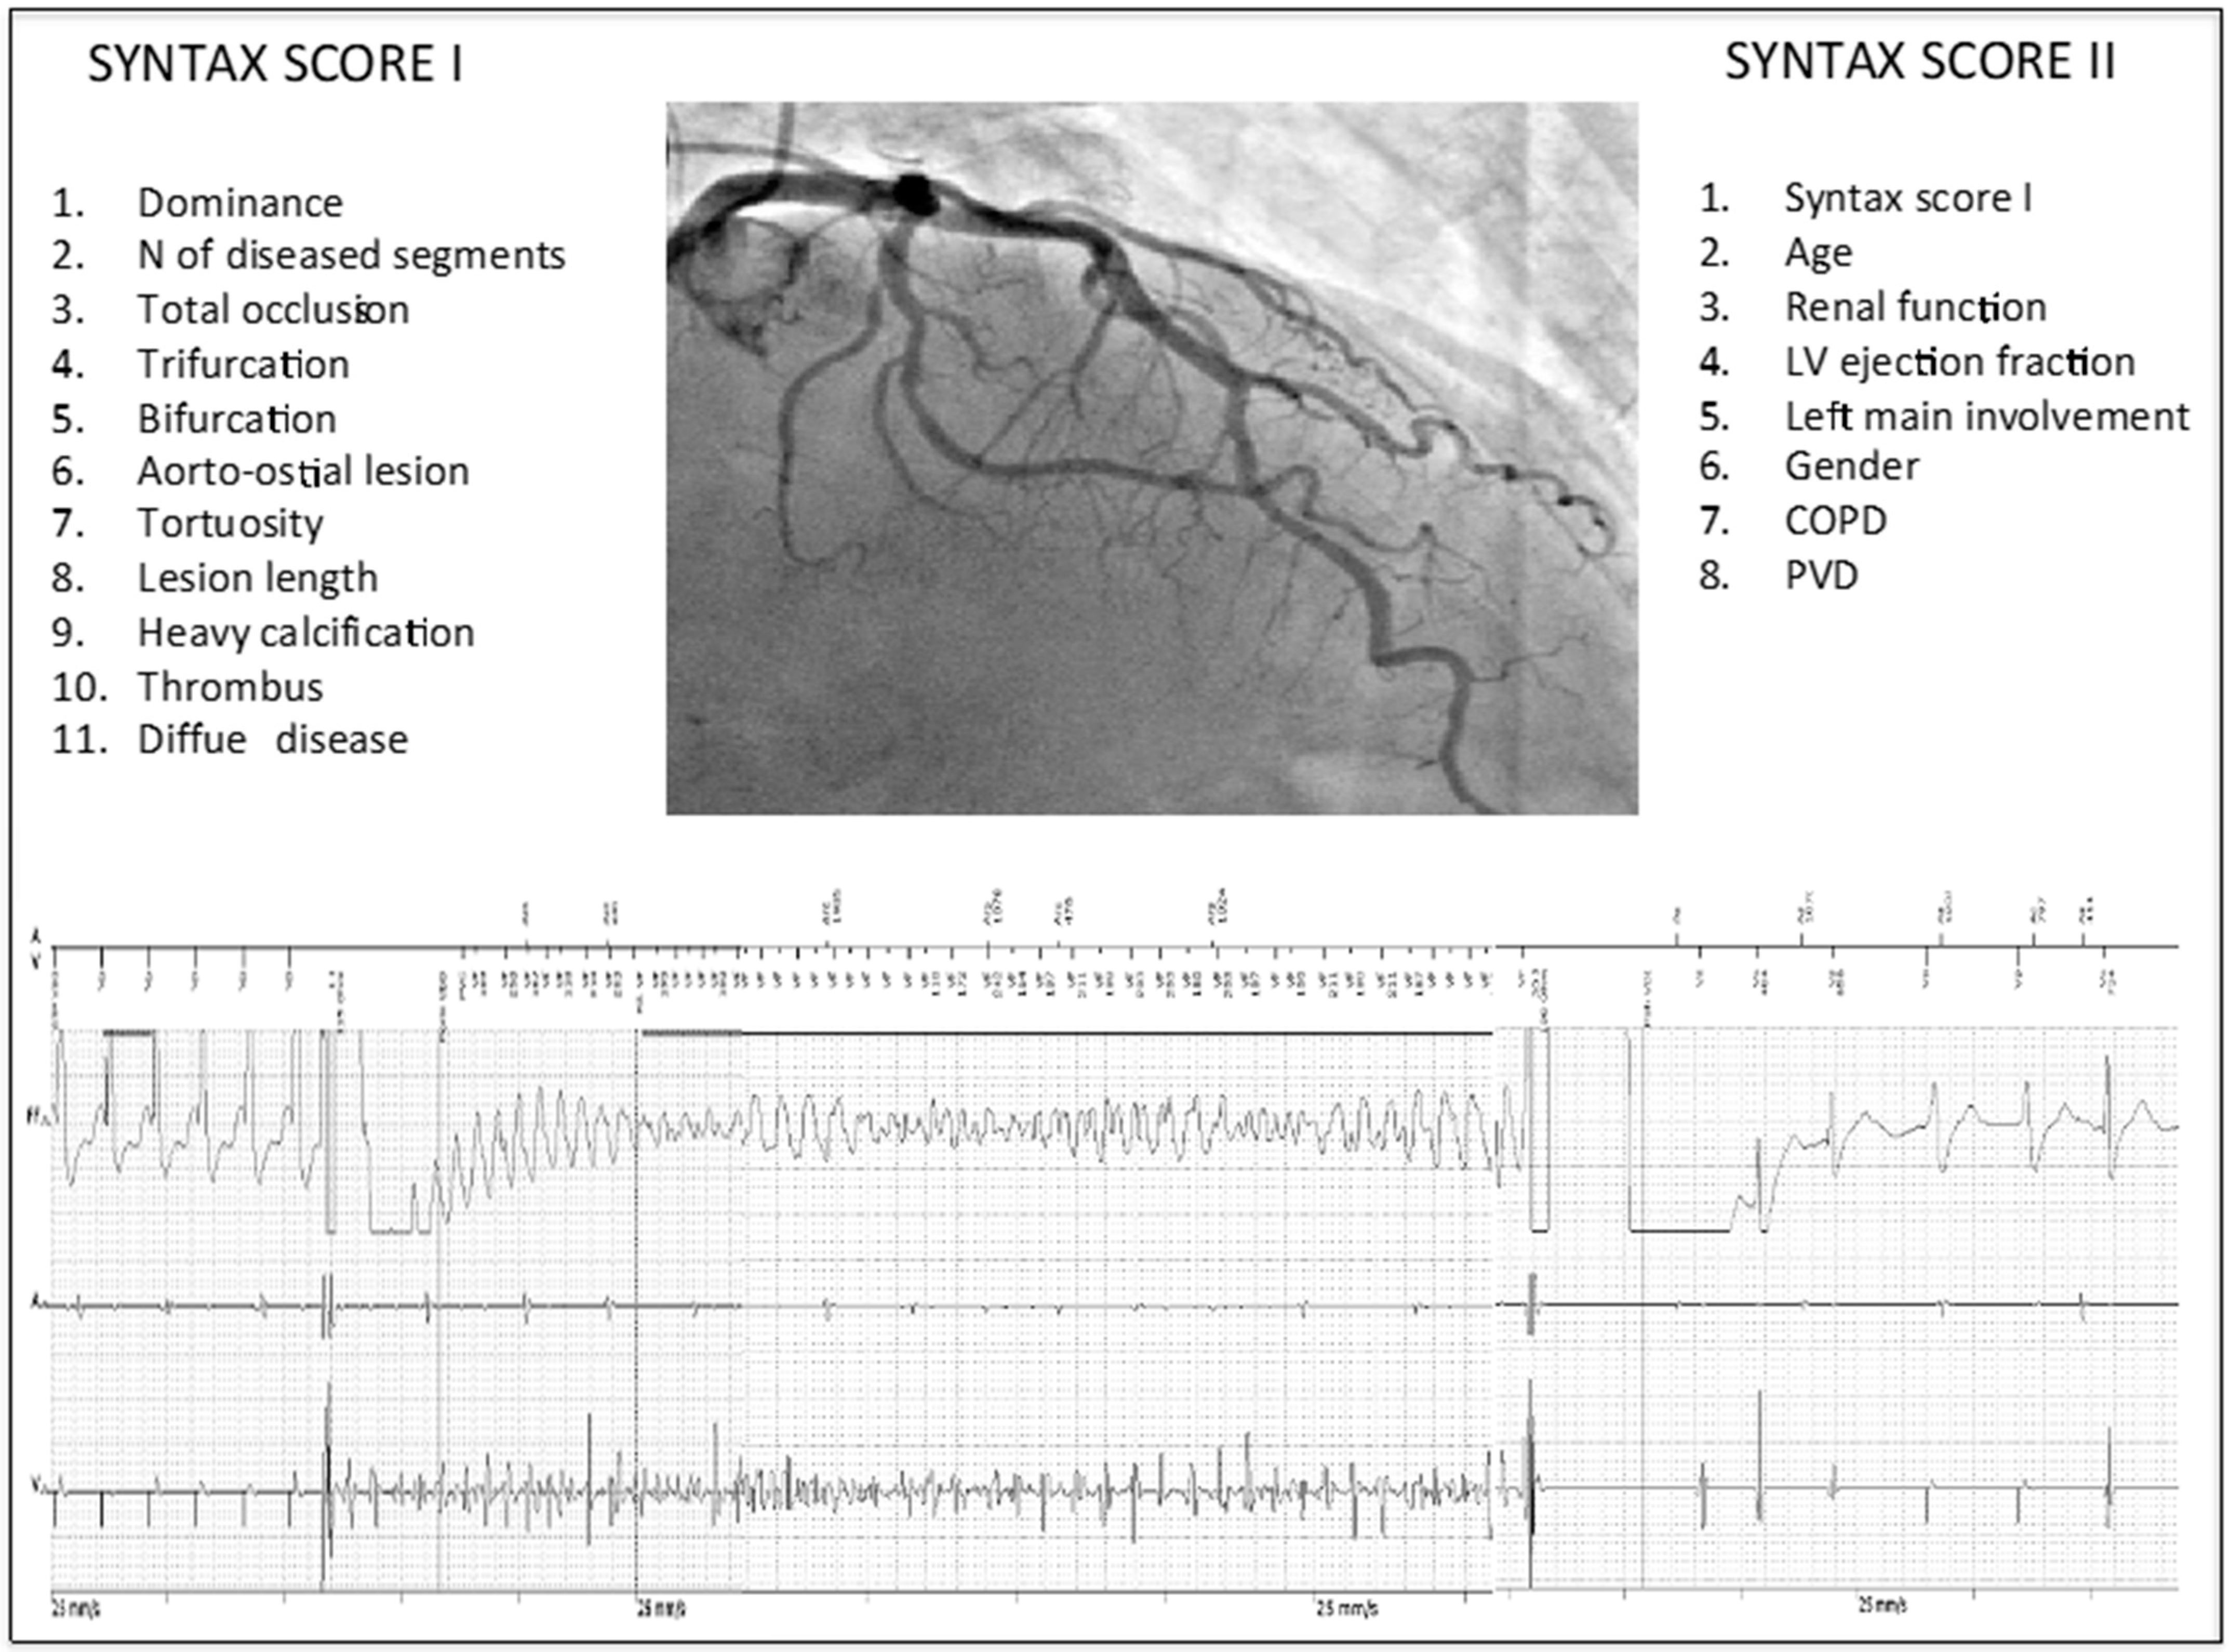

Appropriate ICD Interventions for Ventricular Arrhythmias Are Predicted by Higher Syntax Scores I and II in Patients with Ischemic Heart Disease

| SYNTAX I | 1.04 (1.004–1.07) | 0.029 |

| SYNTAX II | 1.05 (1.01–1.09) | 0.015 |

| SS II | 1.06 (1.01–1.12) | 0.009 |